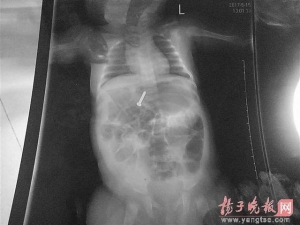

3个月大女婴误吞螺丝钉 消化道异物很危险 3个月大女婴误吞螺丝钉 消化道异物很危险 … [详情] -